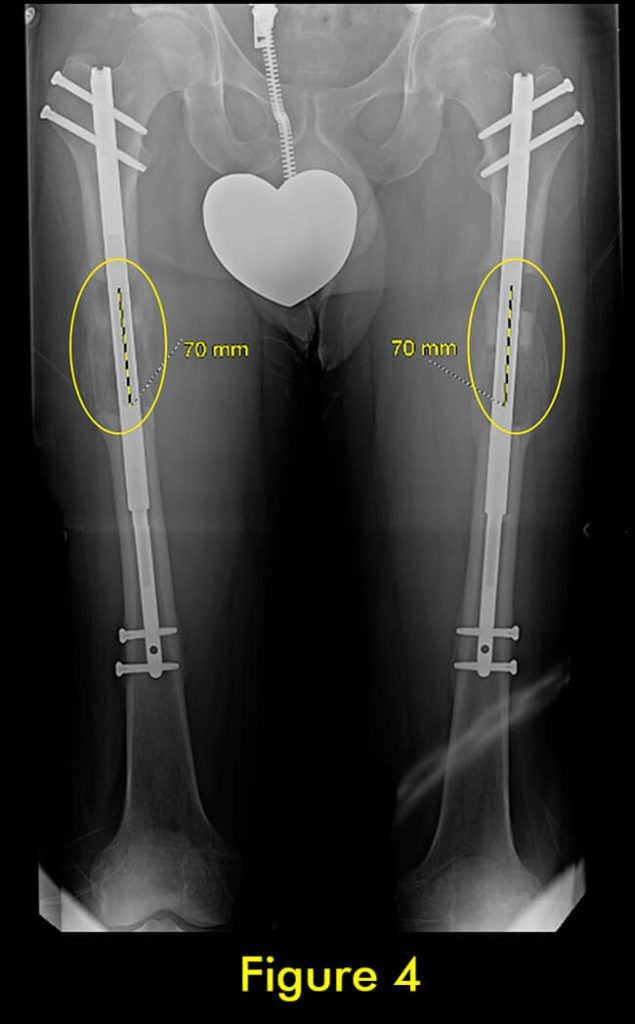

过早合并示意图1

图1:延长量细微差异

过早合并示意图2

图2:X光片确认诊断

随着胫骨的延长,腓骨也必须延长。植入式加长装置仅延长和固定胫骨。腓骨必须固定在胫骨上,以便它与胫骨一起拉长。如果腓骨固定不固定或固定不充分,它不会像胫骨那样拉长,并会导致严重的后果,包括脚踝半脱位和关节炎以及膝盖屈曲挛缩。

固定方法至关重要。许多外科医生只将腓骨的下端固定在胫骨上。这会导致腓骨过早巩固,并在其上端从胫骨向下拉和脱臼。固定腓骨两端很重要。大多数外科医生避免这样做,因为这在技术上很难做到。

我们为所有患者的腓骨两端固定。植入式加长时,腓骨必须用螺钉固定在胫骨上;上端有一个螺钉,下端有一个螺钉。螺钉的角度、水平、位置、直径和类型都很重要。一个常见的错误是将螺钉水平放入两块骨头之间。这不足以防止腓骨从脚踝处的胫骨上拉开。这是非常微妙的,即使脚踝腓骨长度的几毫米差异也会给患者带来短期和/或长期后果。切除腓骨的一部分以防止腓骨不分离是另一种应避免的常见方法。它会导致腓骨不愈合,从而导致胫骨以后出现应力性骨折。

此外,它通常不会阻止腓骨从胫骨上拉开。因此,腓骨并发症与植入式延长装置的类型无关,而是与外科医生选择将腓骨固定到胫骨的方法和切割腓骨的方法有关。腓骨愈合的范围可以从过早巩固到完全不愈合。后者通常不需要治疗,只要胫骨牢固愈合。前者需要重复腓骨截骨术。